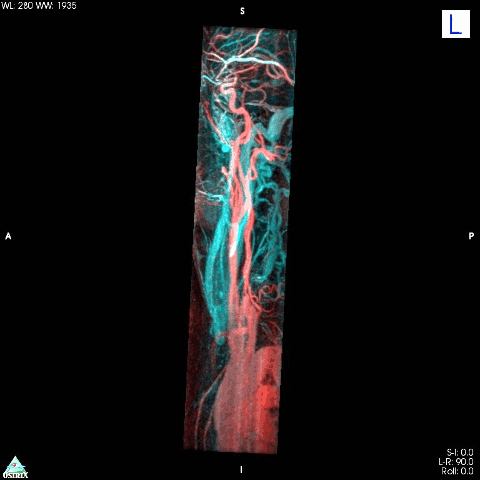

5. Kolorizovaná 3D snímka aorty z magnetickej rezonancie